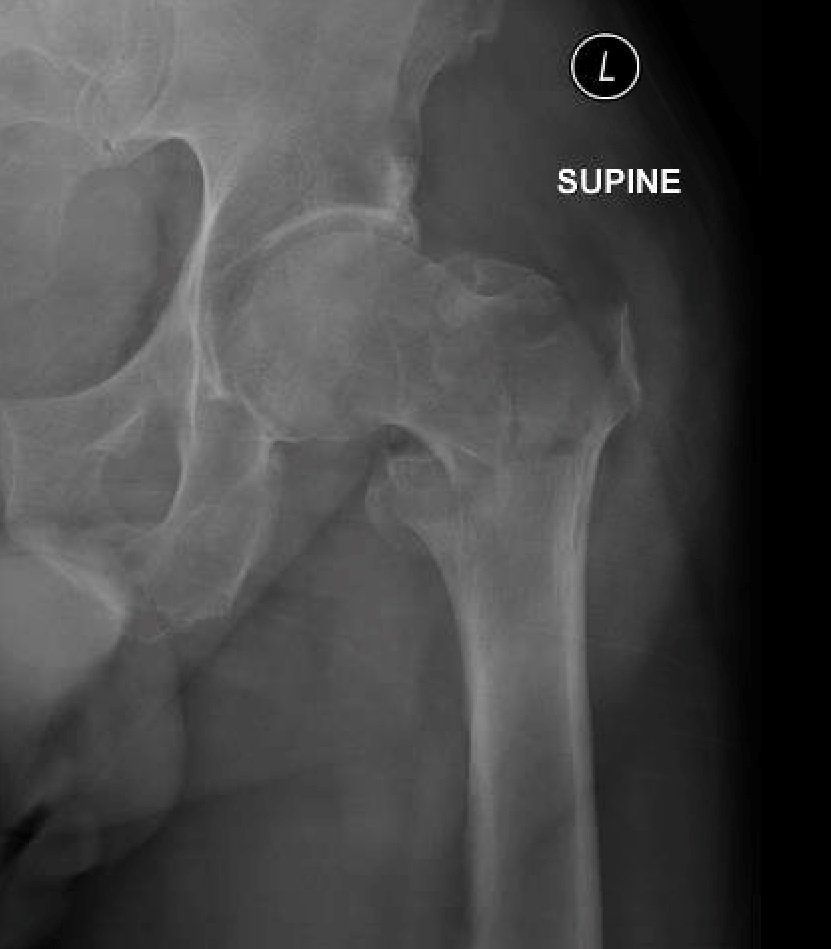

Plain film of the left hip showed acute comminuted displaced intertrochanteric fracture (red arrows) of left femur with varus angulation (green lines) and no dislocation. Greater (blue arrow) and lesser (yellow arrow) trochanters are annotated for reference.